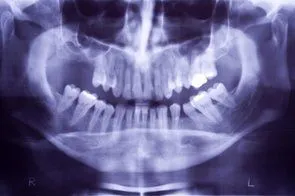

iStock_000002879017XSmall.jpg Loss of posterior teeth may result in excessive forces being placed on your remaining teeth.  Fortunately, the use of dental implants and crowns allow you to replace these missing teeth.  However, the position of the sinus in the upper posterior areas may be too low for proper placement of dental implants.

A simple procedure allows the sinus floor to be repositioned, creating enough space to properly place an implant.  Various grafting materials are used to encourage your bone to grow more quickly into the area, helping to stabilize the dental implant. Replace with your own bone in this area the grafting material as it grows into the area.

Under certain conditions, an even simpler procedure can be utilized.  When possible, the bone remaining under the sinus floor is gently “pushed up”, thus lifting the floor of the “dropped” sinus.  Bone replacement materials are then placed beneath this lifted bone.  Once again the bone materials are replaced as your body grow new bone into this area.